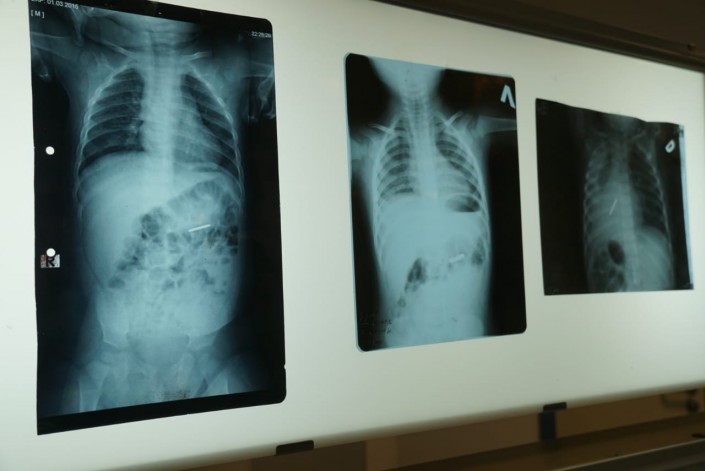

Рентген-снимки ребенка с инородным предметом в организме

По его данным, только за 10 месяцев 2018 года в больнице было отмечено 27 случаев попадания инородных тел в дыхательные пути.

В пищеварительный тракт инородные предметы попадают еще чаще - за 10 месяцев 2018 года отмечен 131 случай.